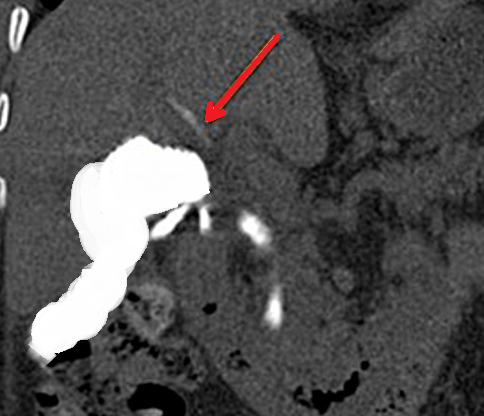

Patient CT, 6th postoperative day. Contrast in the gallbladder fossa. Red arrow — Injured Luschka duct (Courtesy Dr. V. Penopoulos)